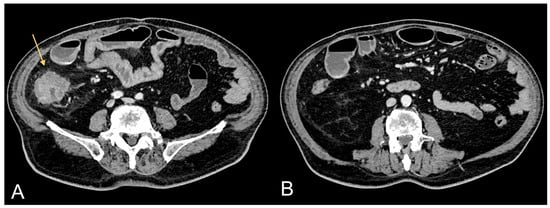

Figure 2.

Contrast-enhanced CT images of a 69-year-old female patient showing HCC in cirrhotic liver (light orange arrow in (A)) and relative excessive amount of VAT (B).